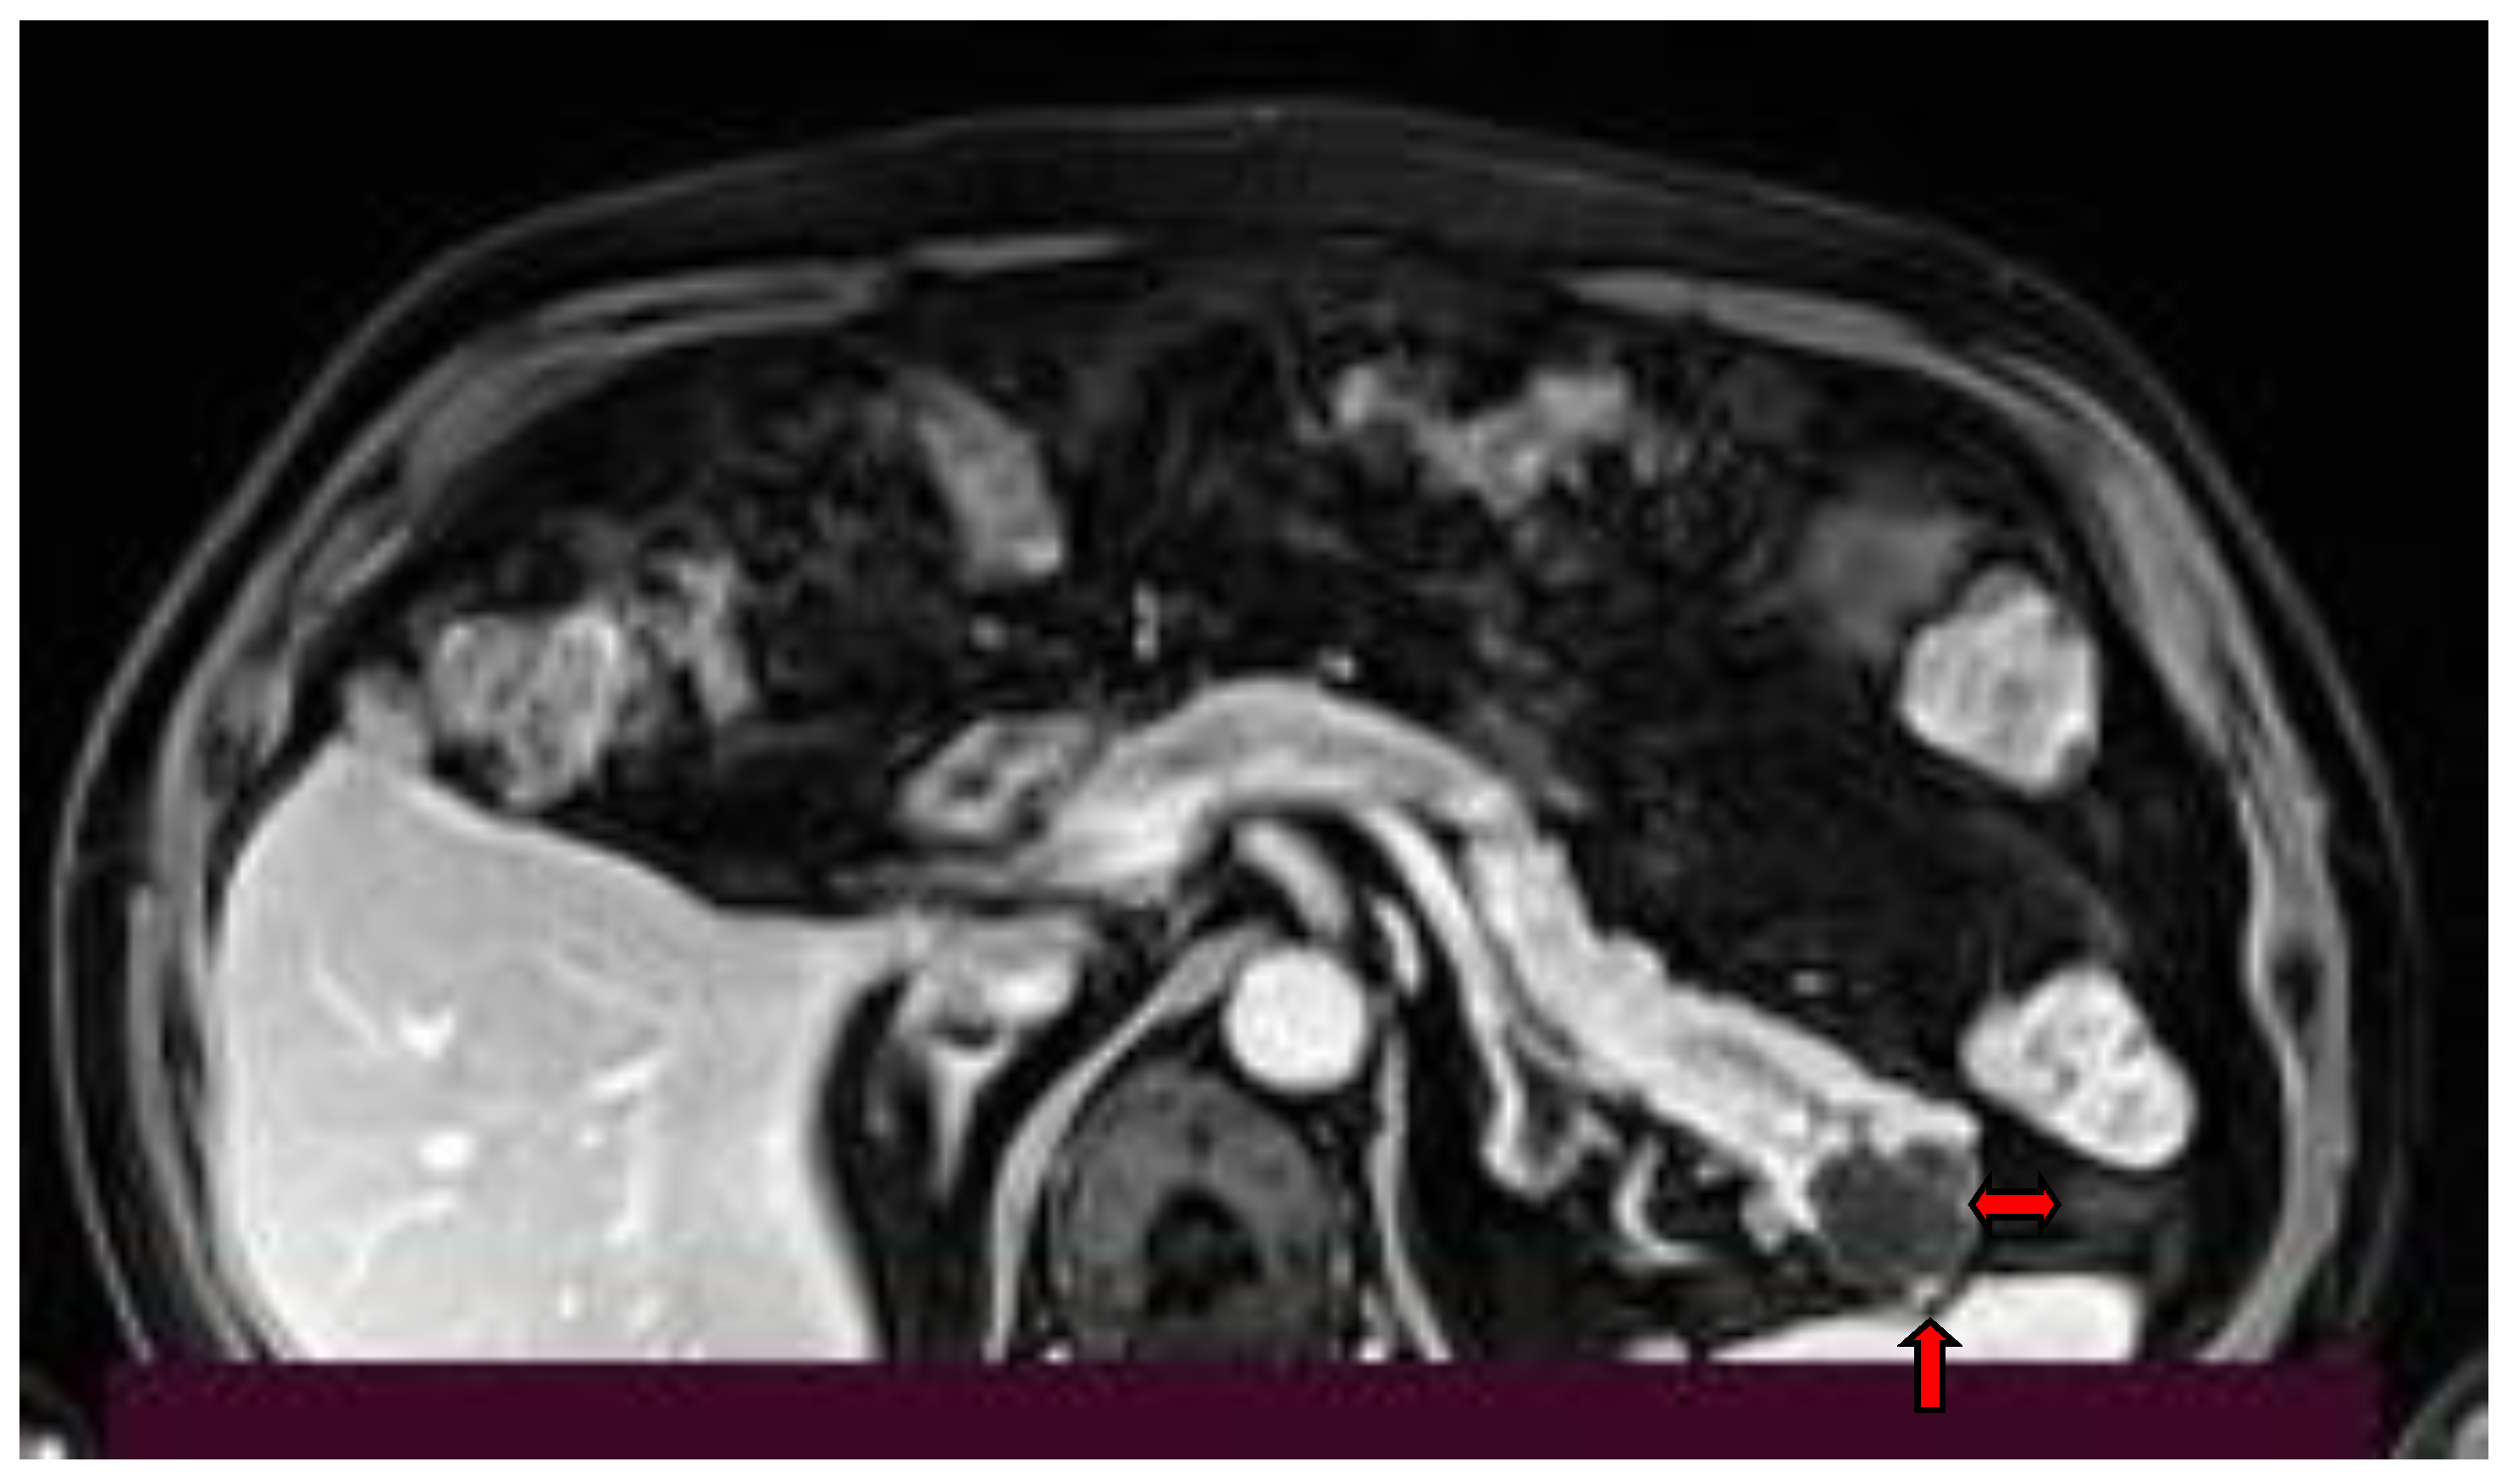

2. Imaging Findings

- Yamada, Y.; Mori, H.; Hijiya, N.; Matsumoto, S.; Takaji, R.; Ohta, M.; Kitano, S.; Moriyama, M. Intraductal papillary mucinous neoplasms of the pancreas complicated with intraductal hemorrhage, perforation, and fistula formation: CT and MR imaging findings with pathologic correlation. Abdom. Imaging 2012, 37, 100–109. [Google Scholar] [CrossRef]